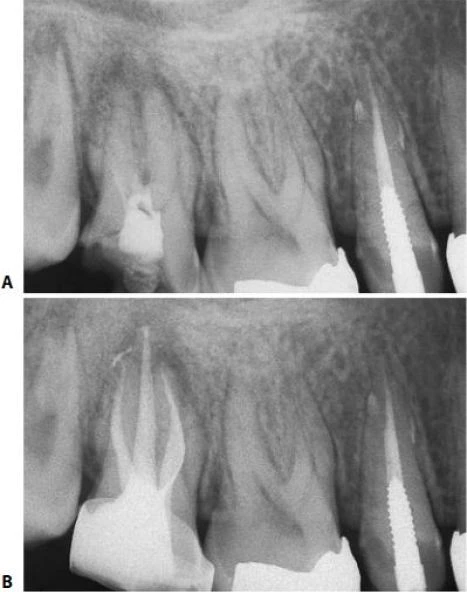

Trên X-quang có thể thấy chân răng hơi cong nhẹ theo chiều gần xa hoặc ngoài trong (hình 5.41).

Hình 5.41. A. Phim X-quang trước điều trị của răng cửa giữa hàm trên bên phải. Lỗ chóp nằm trên cùng một mặt phẳng trên đường đi của tia X: nó có thể đối diện với mặt trong hoặc mặt ngoài. B. Phim X-quang thứ hai chụp theo hướng gần-xa cho thấy đoạn cong đối diện với mặt ngoài. Việc điều trị tủy được hoàn tất, giữ nguyên góc chụp cho phép nhìn thấy được điểm cuối cùng trên X-quang của ống tủy. C. Phim sau điều trị. Lưu ý rằng chỉ với góc chụp này mới thấy được hình ảnh tổn thương nhỏ tại chóp chân răng. D. Phim sau điều trị được chụp theo tiêu chuẩn hình chiếu. Lưu ý rằng vật liệu trám ống tủy dường như bị ngắn đi chừng 2mm và tổn thương cũng đã lành.